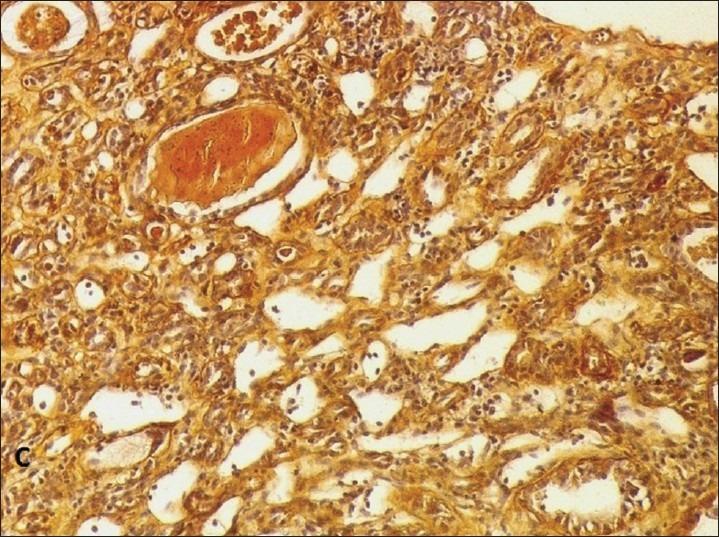

Renal cortical necrosis: A rare complication of Plasmodium vivax malaria.

A young female with Plasmodium vivax malaria presented with anemia, hyperbilirubinemia, thrombocytopenia, and advanced renal failure. She remained anuric for more than 3 weeks. Kidney biopsy confirmed the diagnosis of acute cortical necrosis. During follow-up, she became dialysis independent, but remained in stage 4 chronic kidney disease (CKD) at 3 month. P. vivax is supposed to be benign in nature, but can lead to rare and severe complication like renal cortical necrosis and progress to CKD.